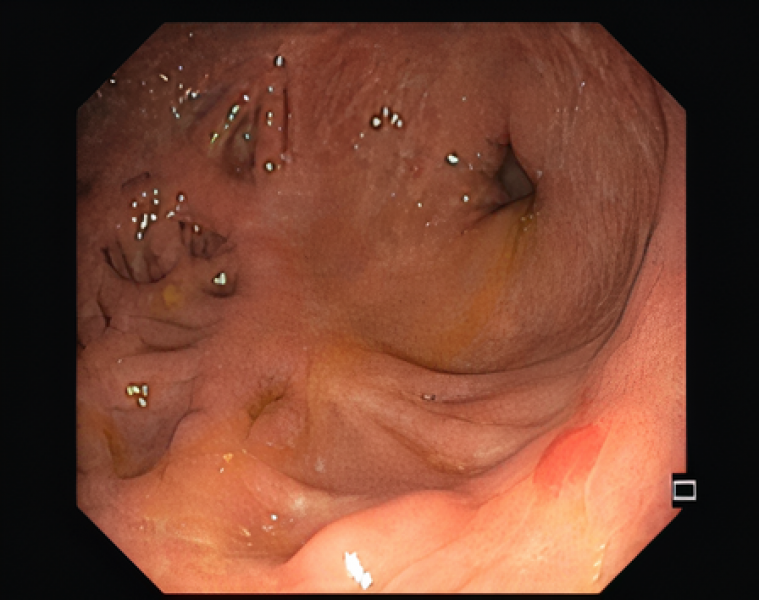

Gastric Crohn's disease